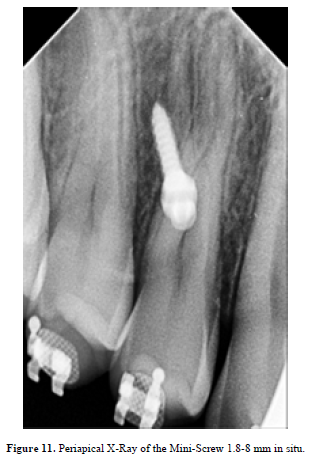

TADs are of a paramount importance within treatment of scissors-bites (Figure 9,10), scheming the treatment plan is supposed to include the TADs pulling (Figure 11,12 & 13).